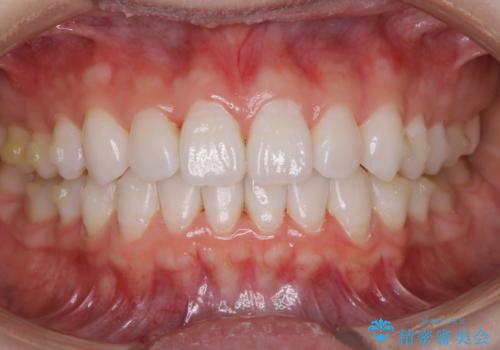

インビザラインで矯正治療中に、クリーニングを行ったbeforeafter写真です。

矯正治療中は、虫歯や歯周病のリスクが高くなったり、長い時間マウスピースを着用することにより、ステイン(着色)がしやすくなることがあります。

そのため矯正治療中は、(マウスピース矯正・ワイヤー矯正共に)クリーニングを行い、こまめに汚れを取り除き、お口のケアをすることが大切です。